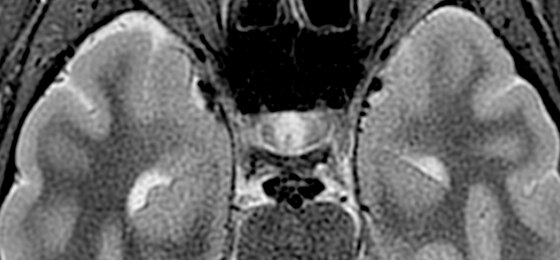

Make no substitutes for image quality

Clearly consistent images

Simply better compared to conventional coil technology.